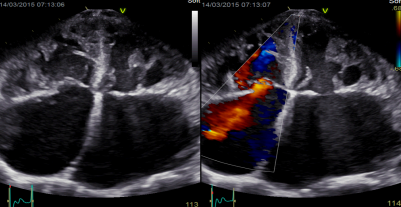

3.VirtualApex虚拟心尖技术:

VirtualApex虚拟心尖技术——相控阵探头提供的近场宽成像视角,能够扩大心尖部结构成像范围,并消除近场干扰,使心脏右室前壁、心尖部等近场部位的诊断更容易。